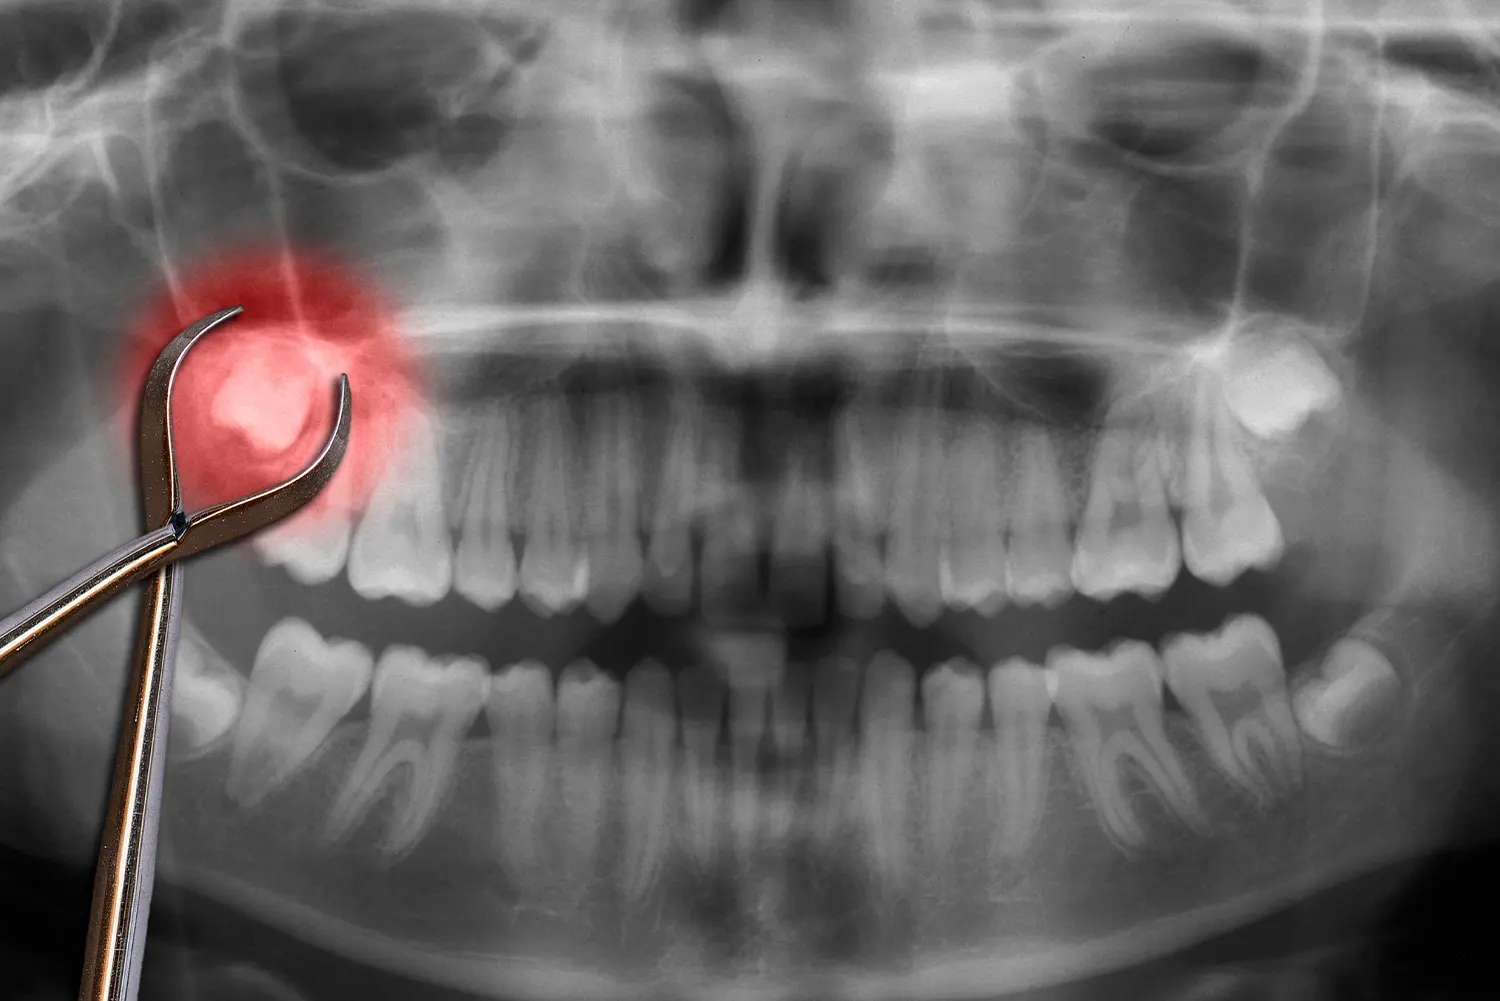

Wisdom tooth pain can be intense and distracting. If your wisdom teeth are impacted, infected, or crowding other teeth, it’s important to book an appointment with a low income dentist right away. Left untreated, problematic wisdom teeth can lead to swelling, infection, damage to nearby teeth, cysts, and even bone loss. Early evaluation and treatment can prevent complications and protect your long-term oral health.

During the procedure, the dentist carefully removes the wisdom tooth (or teeth) causing the issue. If the tooth is impacted beneath the gums, a small incision may be made to access it. Once removed, the area is cleaned and, if necessary, stitched to promote proper healing.

Surgical Extraction: For impacted wisdom teeth that are partially or fully trapped beneath the gum or bone, a surgical extraction is required. This involves a small incision to safely access and remove the tooth.

Full Bony Impaction Removal: If the wisdom tooth is completely encased in bone, a more advanced surgical approach is used to section the tooth and remove it in pieces for safer extraction.

Even if you’re not currently experiencing pain, your dentist may recommend removal if X-rays show that your wisdom teeth are likely to cause future problems. Early removal can often prevent more serious complications down the road.